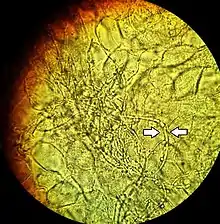

Diagnosis of a yeast infection is confirmed either via microscopic examination or culturing. For identification by light microscopy, a scraping or swab of the affected area is placed on a microscope slide. A single drop of 10% potassium hydroxide (KOH) solution is then added to the specimen. The KOH dissolves the skin cells, but leaves the Candida cells intact, permitting visualization of pseudohyphae and budding yeast cells typical of many Candida species.